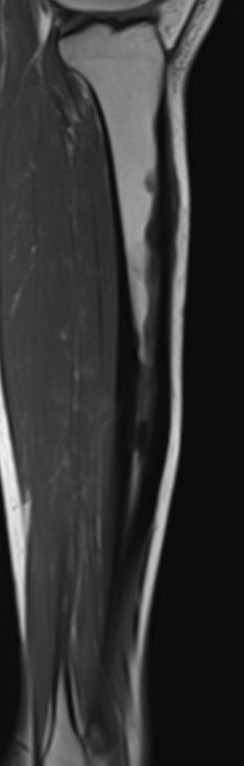

MRI

Khanna et al Skeletal Radiol 2008

- 24 cases of OFD / adamantinoma

- adamantinomas tend to be larger / cortical destruction / complete marrow involvement